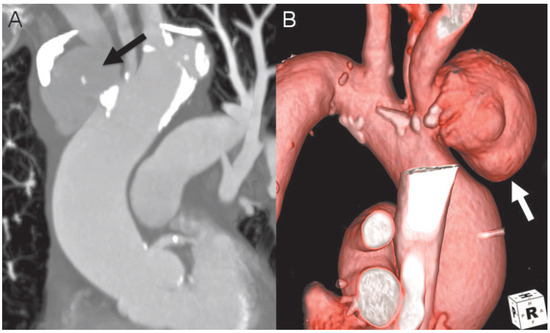

The contrast-enhanced thoracic computed tomography on admission revealed a sub-acute aortic rupture (Figure 1A,B) at the base of the brachiocephalic trunk with subsequent false aneurysm.

Figure 1. Contrast-enhanced thoracic computed tomography with multi-planar reconstruction (A) and surface-rendering reconstruction (B) showing a sub-acute aortic rupture at the base of the brachiocephalic trunk (black arrow) with subsequent false aneurysm (white arrow).